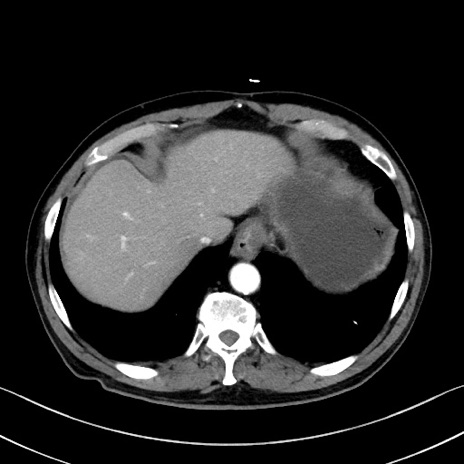

症例35(横断像)

【症例】70歳代 男性

【主訴】腹部膨満、嘔吐

【現病歴】昨日より腹部膨満感出現。本日増悪し、仙痛出現。嘔吐あり、受診。

【既往歴】糖尿病、胆摘後

【身体所見】BP 149/80mmHg、HR 74/min、BT 35.9℃、腹部:膨満、軟、圧痛なし。腸雑音減弱あり。上腹部正中切開瘢痕あり。

【データ】WBC 13500、CRP 1.72